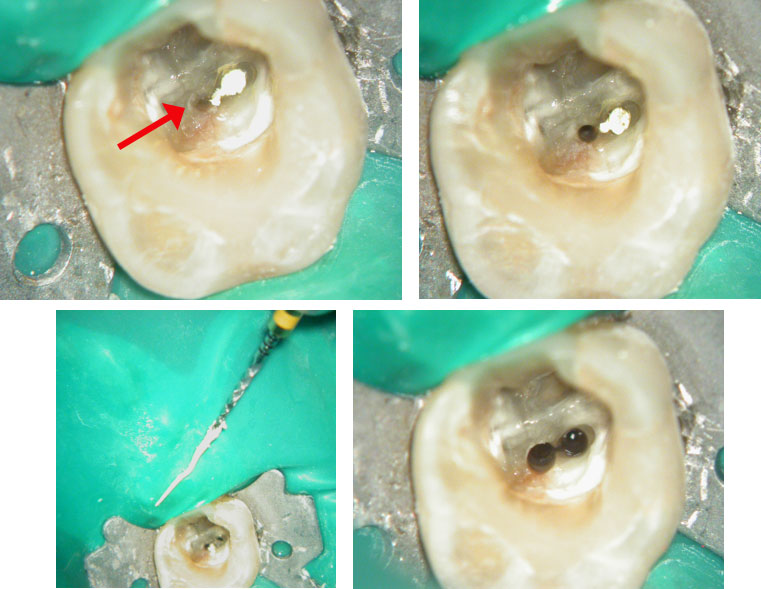

Red arrow shows calcification covering the MB2. Removal of this calcification with ultrasonics reveals the missed MB2(yellow arrow)

5 canals cleaned, shaped and obturated after 10 days of calcium hydroxide. MB1 and MB2 had seperate portals of exit. DB2 merged intoDB1. Palatal two portals of exit.